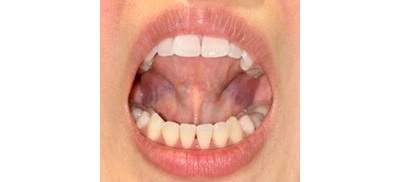

リラックスした時にお口がポカンとしている

一見お口が閉じているようにも見えるが、よく観察すると唇が少し開いている